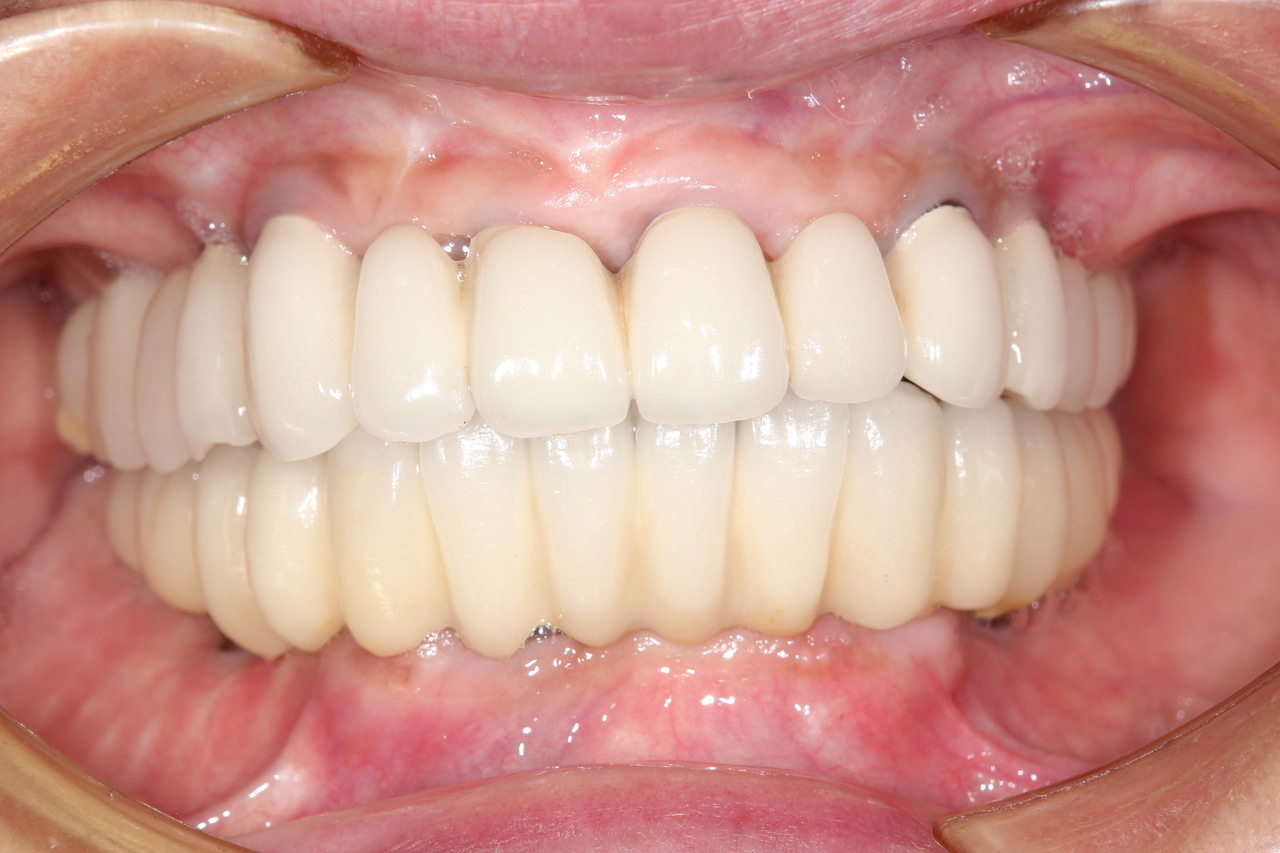

多くの歯を失ったケース

固定式タイプ

・5~8本のインプラントによって自分の歯のように噛めるよう修復

多くの歯を失った場合。

手術でインプラントを埋める。

人工歯を装着します。

インプラント治療で修復。